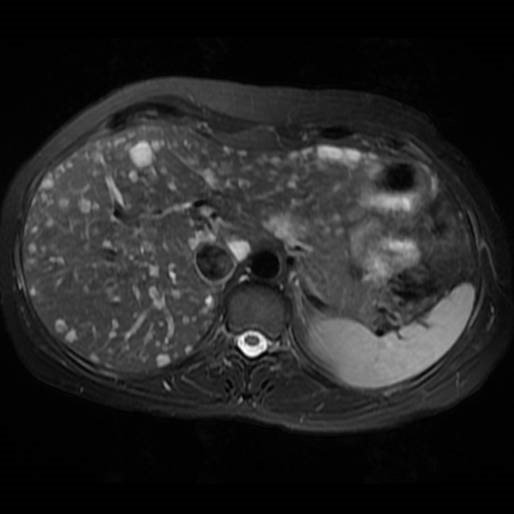

• Xarakterik görüntüləmə əlaməti yoxdur, əksər əlamətləri metastazları xatırladır (normal Qc fonu, çoxsaylı düyünlər, USM- də hiper- və ya hipoexoik, kapsulyar retraksiya, periferik haşıyə, T1-də hipointens, T2-də hiperintens, kalsifikasiya).

• Diaqnozu dəqiqləşdirmək üçün biopsiya lazımdır.

Epitelioid hemangioendotelioma